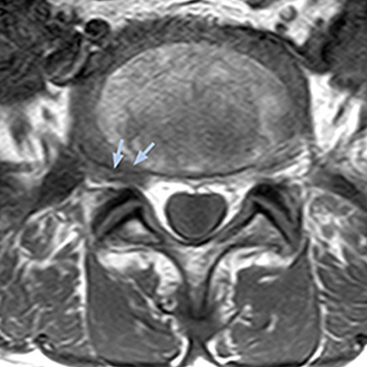

“The intra-luminal signal of veins, especially around the intervertebral space, can be suppressed well with NerveVIEW. As a result, we can easily observe the detailed nerve structure around the posterior ganglion,” he says. “This is why we use 3D NerveVIEW for intraforaminal stenosis and extraforaminal stenosis/herniation (lateral disc herniation). On the other hand, if herniation is suspected to exist inside the dorsal root ganglion (DRG), balanced TFE or ProSet-FFE is applied. NerveVIEW is not suitable for evaluating the median type of herniation.” The SE-EPI DWI-based method for MR neurography works well for large FOV exams like whole-body MRI, but focal examination of nerves is often limited by the attainable spatial resolution (both inplane and slice direction) and geometric distortion. “3D NerveVIEW achieves higher in-plane resolution – close to our other routine spine sequences – and the source images can be used instead of adding a fat-suppressed T2-weighted sequence,” Tanji says.

According to Tanji, methods such as ProSet FFE, STIR or 3D VISTA are anatomically nonselective because background signals, for instance from blood vessels, often interfere with nerves, which hampers evaluation of details, especially at the peripheral side of the nerves.